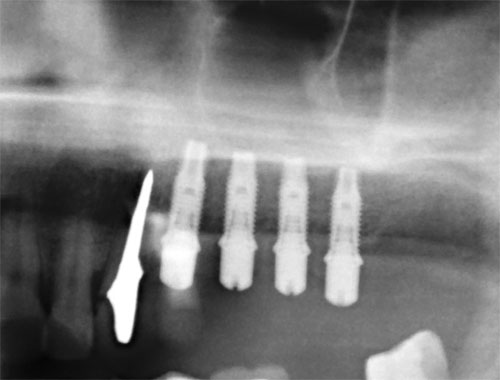

![]() Синус-лифтинг (поднятие дна гаймеровой пазухи). Данная процедура относится только к верхней челюсти. Проводится в случаях недостаточной высоты кости между краем костного гребня верхней челюсти и дном гаймеровой (верхнечелюстной) пазухи. Различают открытый и закрытый синуслифтинг по способу доступа к пазухе. Закрытый — это доступ через отверстие импланта, а открытый — это боковой доступ через преддверие полости рта. Принцип операции в том, что через любой из доступов, в пазуху вводится костное вещество, которое превращается в собственную кость в течение полугода. В зависимости от толщины альвеолярного отростка зубные имплантаты могут быть установлены либо одновременно с выполнением синус-лифтинга, либо через некоторое время после заживления участка. статья «Синус-лифтинг» добавлена 2008-11-15 года